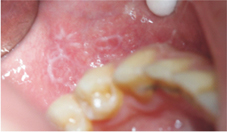

口腔扁平苔癬是一種慢性發炎性的口腔黏膜病變,為人體免疫失調而造成的局部自體免疫疾病,發病率約占總成年人口的百分之一到二;在性別比例上,女性多於男性,特別是中老年女性。在口腔內,口腔扁平苔癬好發於頰黏膜、舌頭、牙齦、嘴唇,且多為兩側性或多發性出現。在臨床上可以再區分為六種型態,分別是:網狀型(reticular type)、丘疹型(papular type)、斑狀型(plaque type)、萎縮/糜爛型(atrophic/erosive type)、潰瘍型(ulcerative type)以及水?型(bullous type),並且這六種型態並非只會單獨出現,常可能有其中的二到三種同時發生於口腔中。網狀型,顧名思義會看到白色網狀的條紋交錯排列(如:圖一);丘疹型則會出現小顆粒的突起;斑狀型則呈現白色的斑塊(如:圖二),此三種型態可歸為非糜爛型的口腔扁平苔癬,除了外觀上的變化外,往往沒有明顯的臨床症狀;糜爛型的口腔扁平苔癬則會在黏膜上看到一些紅色的斑塊,且周圍伴隨有白色的放射線狀條紋(如:圖三),而水?型相對於其他幾種型態,則較為少見。其中,糜爛型和潰瘍型的口腔扁平苔癬,常伴隨有疼痛或是較為敏感等口腔黏膜不適的症狀,這些不適的症狀往往是患者前往就診的原因。另外,有些患者的口腔牙齦也會有發炎紅腫的現象,稱為「脫屑性牙齦炎」(desquamative gingivitis)。

圖一、網狀型口腔扁平苔癬